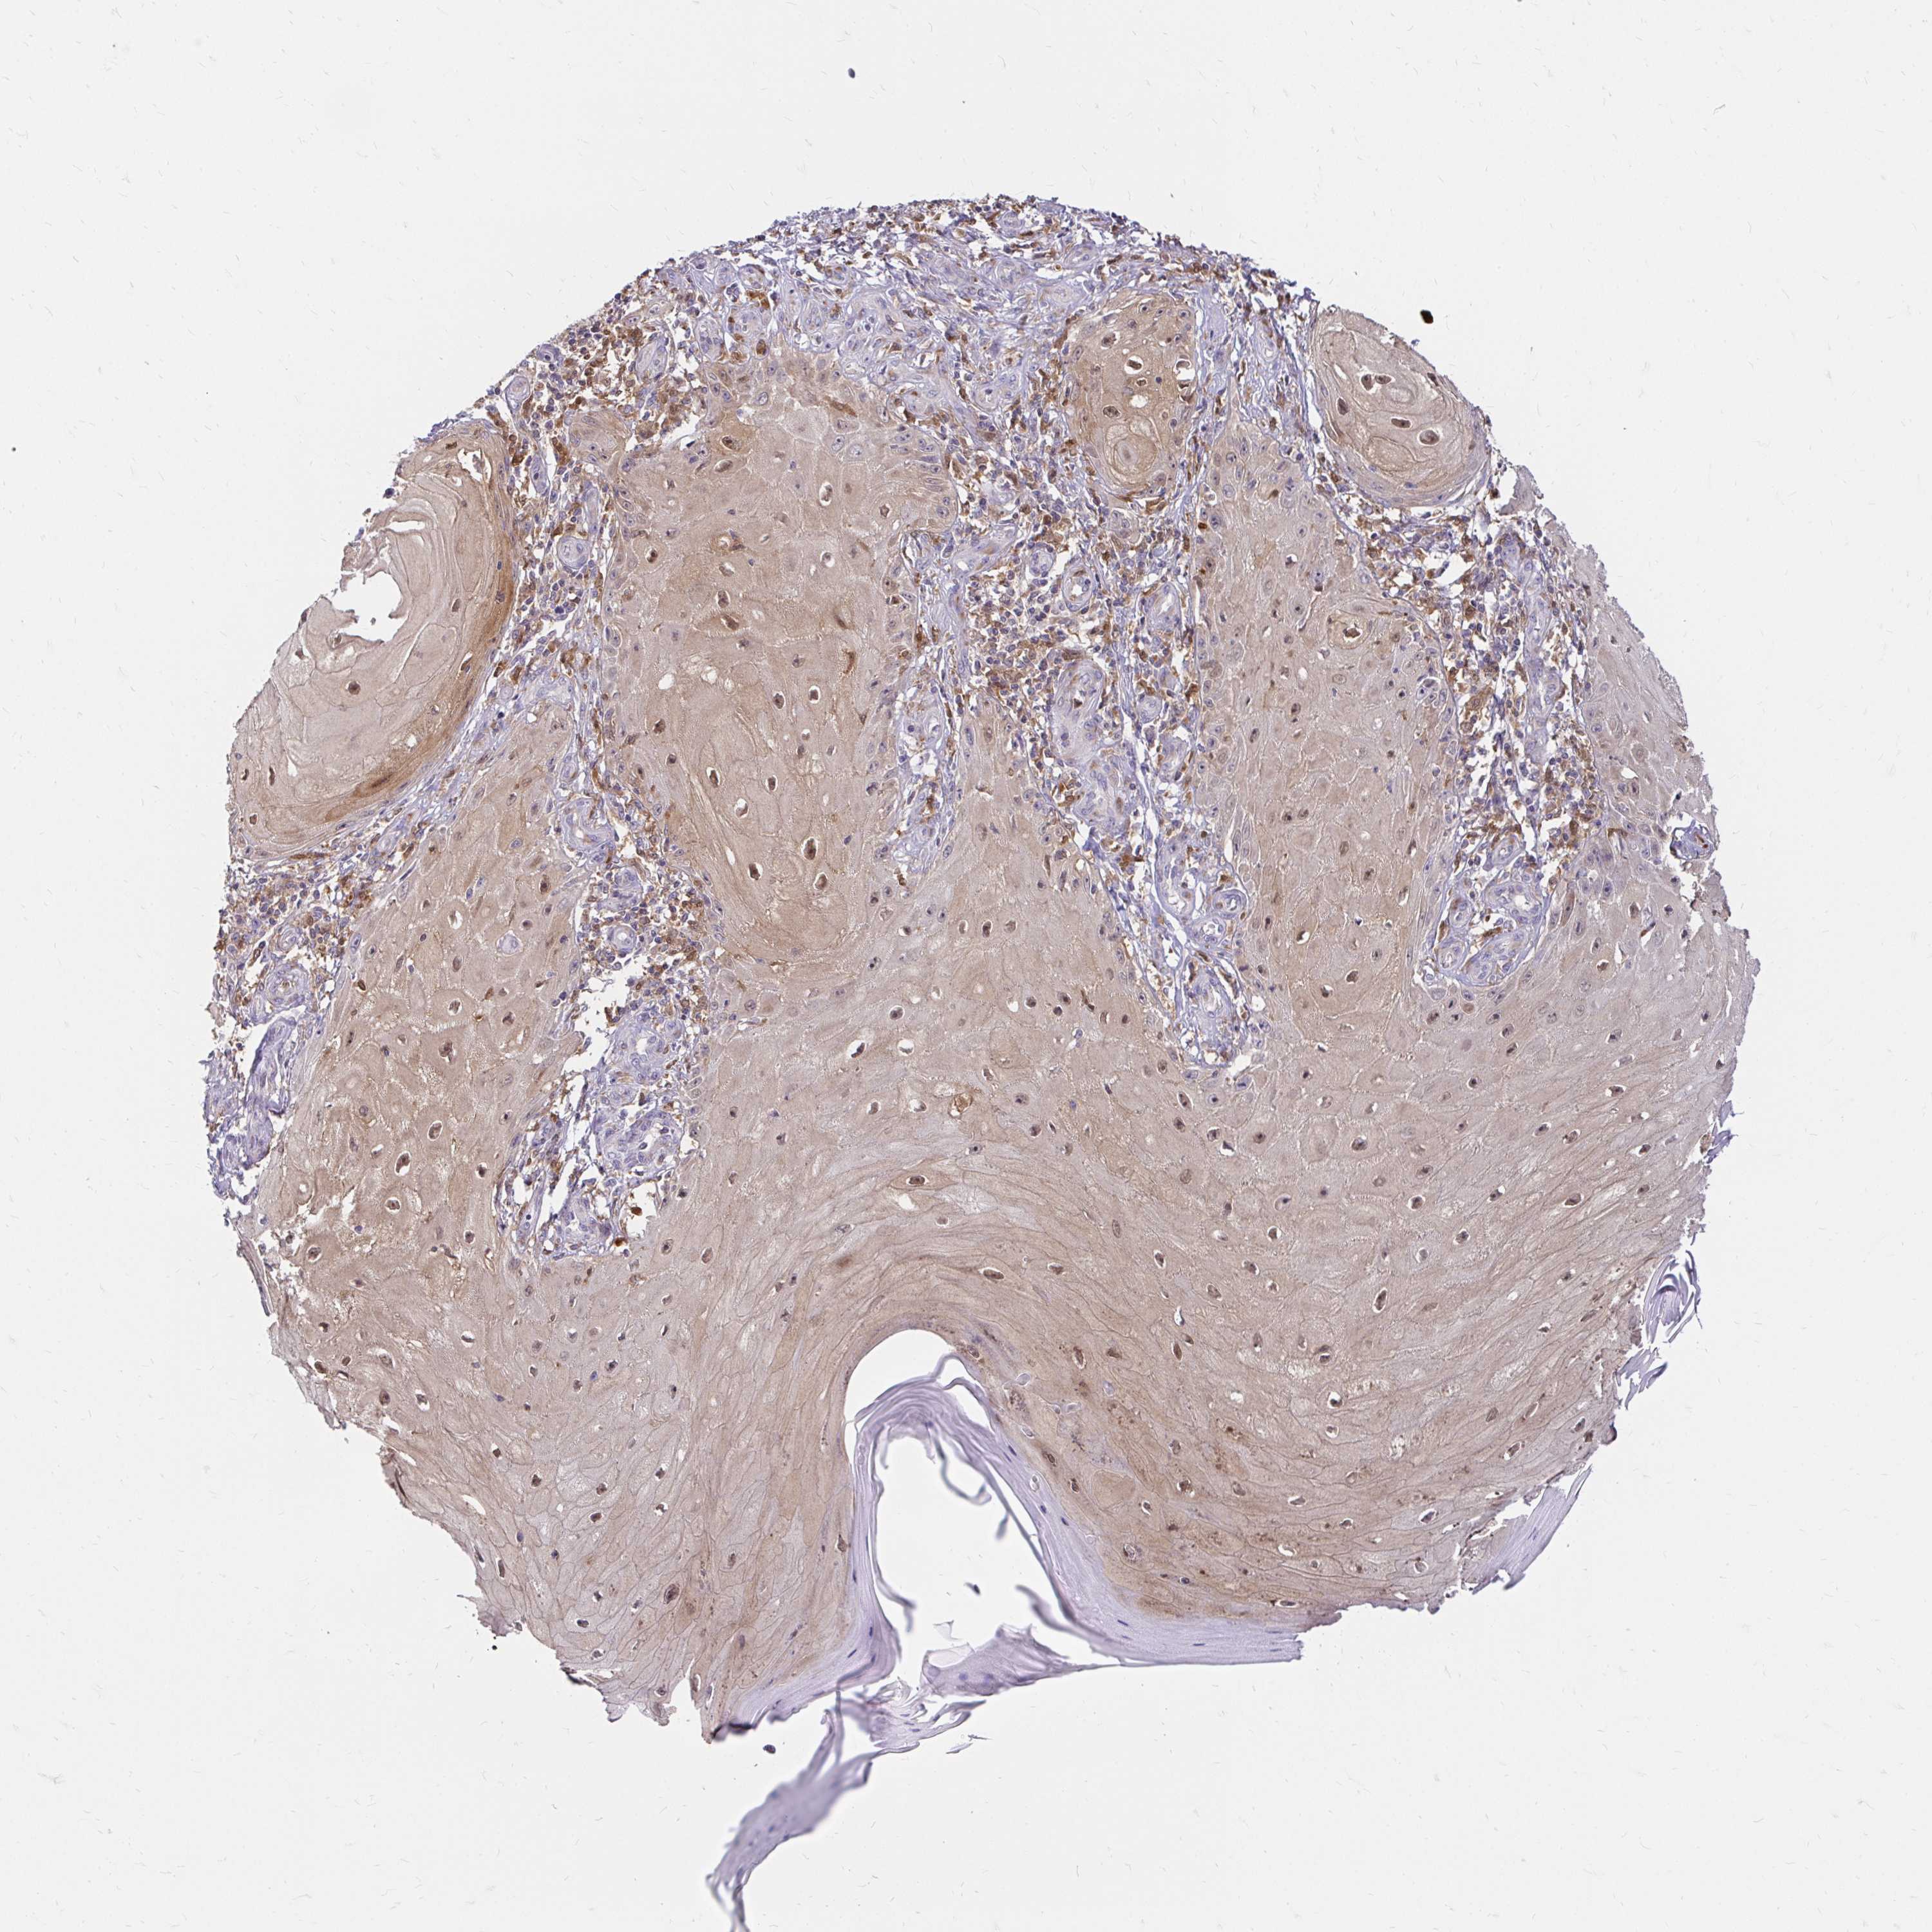

SKIN CANCER - Protein expressioni

A mouse-over function shows sample information and annotation data. Click on an image to view it in a full screen mode. Samples can be filtered based on level of antibody staining by selecting one or several of the following categories: high, medium, low and not detected. The assay and annotation is described here.

Antibody staining in the annotated cell types in the current human tissue is reported as not detected, low, medium, or high, based on conventional immunohistochemistry profiling in selected tissues. This score is based on the combination of the staining intensity and fraction of stained cells.

Each image is clickable and will lead to virtual microscopy that enables deeper exploration of all samples and also displays staining intensity scores, fraction scores and subcellular localization as well as patient and tissue information for each sample.

Basal cell carcinoma

Squamous cell carcinoma, NOS

Squamous cell carcinoma in situ, NOS

Squamous cell carcinoma, metastatic, NOS

Adnexal tumor, benign